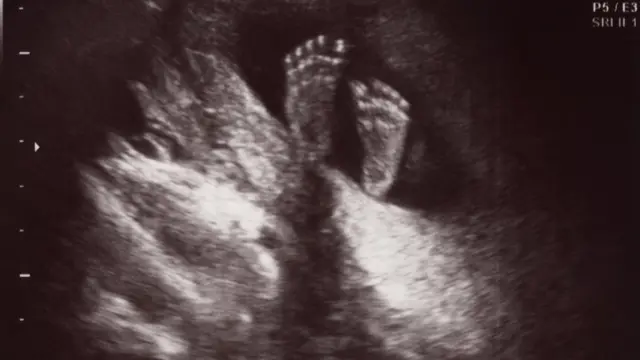

Paola observó parte del proceso cuando logró tomarse ecografía en 3D. En las imágenes, "vi cómo mi hijo se iba mutilando mientras crecía". Al poco tiempo de gestación ya había perdido un brazo.

"Mi marido dijo, no. Yo tampoco me quería quedar con esa imagen. Sabía que no tenía su carita, pero me acordé que desde la cintura estaba entero, y les pedí que me mostraran sólo las piernas. Así que lo taparon completo y me lo acercaron y le vimos sus patitas".